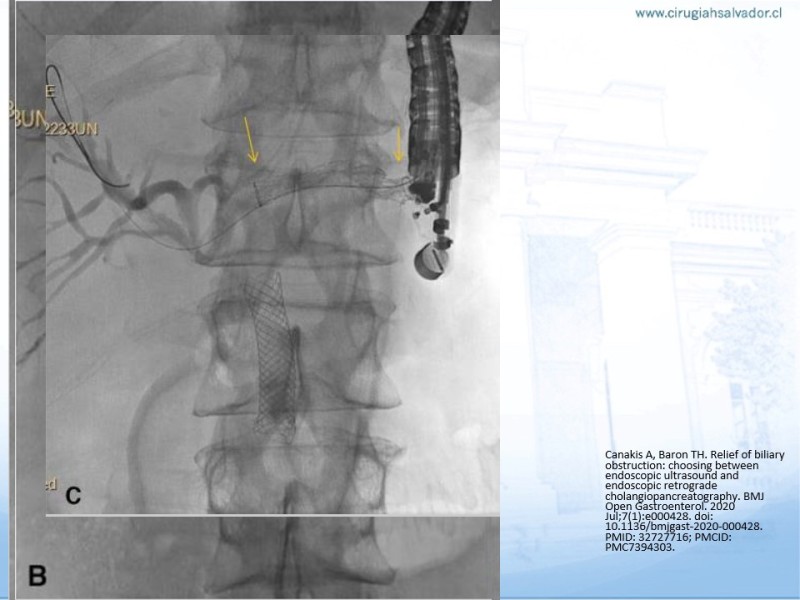

Actualización del drenaje de vía biliar